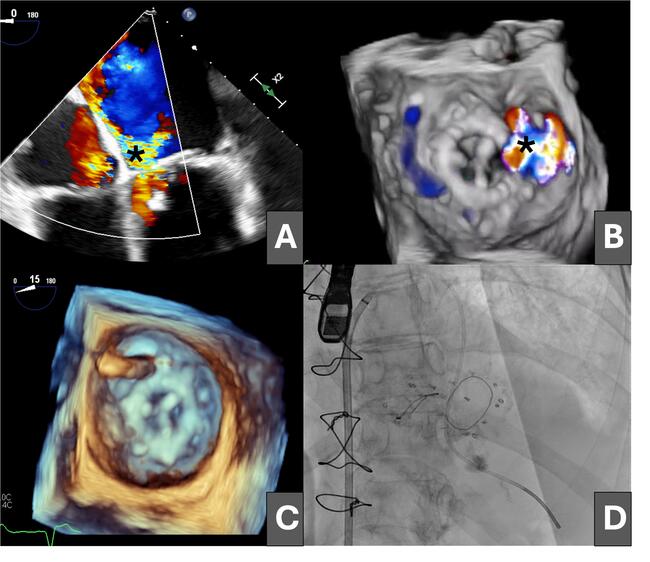

Off‑Label Use of a Ventricular Septal Defect Occluder for Large Mitral Paravalvular Leak in the Early Postoperative Period: A Case Report

Video Supplement to "Off‑Label Use of a Ventricular Septal Defect Occluder for Large Mitral Paravalvular Leak in the Early Postoperative Period: A Case Report" (Clinical Image).

Video 3. Three-dimensional transgastric reconstruction of the final result with the ventricular septal defect occluder device.